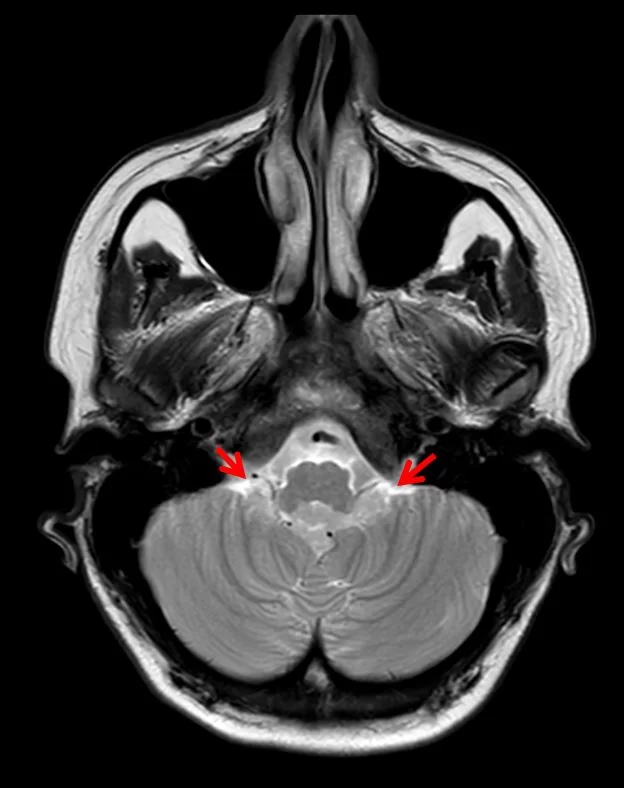

Τα επενδυμώματα ανήκουν στα γλοιώματα και αναπτύσσονται τυπικά εντός ή πλησίον του επενδύματος του κοιλιακού συστήματος του εγκεφάλου. Η πιο συνηθισμένη θέση είναι η περιοχή της παρεγκεφαλίδας (Εικόνα 1 & 2).

Τα ενδοκρανιακά επενδυμώματα παρουσιάζουν μέγιστη επίπτωση στην παιδική ηλικία, με μέση ηλικία διάγνωσης τα πέντε έτη. Στους ενήλικες, τα επενδυμώματα είναι πιο συχνά στην περιοχή του νωτιαίου μυελού.